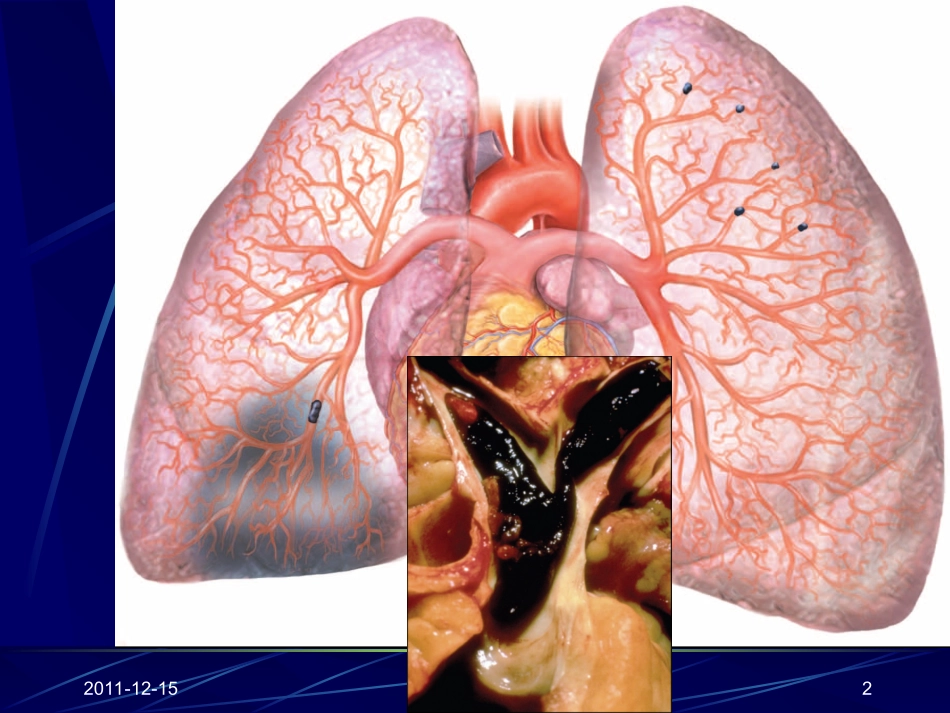

急性肺血栓栓塞症规范化诊断与治疗威海市中医院2011-12-152分享一个病例先介绍一个病例:患者王某,女,64岁,农民。因突发憋喘2小时,于2010年2月5日收住院,当时是在行走过程中发病,表现为胸闷、出汗、憋喘、头晕,并有一过性晕厥,醒后憋喘更为明显。病史中有外伤后左下肢静脉曲张三年。2011-12-153临床资料入科时心率120次/分,血压80/64mmHg,并一度降至70/44mmHg,呼吸急促40次/分,SO283-95%。血气分析:PH7.25,PaCO251mmHg,PaO257mmHg,HCO3-22.4mmHg,lac3.4mmol/L,Hct47%。ECG呈SIQIIITIII,V1呈qR。D-二聚体阳性,肌钙蛋白I阴性。肺CT造影:右肺动脉主干及多支血管栓塞,胸腔积液。2011-12-1542011-12-155Thesepulmonaryemboliremovedatautopsylooklikecastsofthedeepveinsofthelegwheretheyoriginated.2011-12-156名词与定义肺栓塞(pulmonaryembolism,PE)肺血栓栓塞症(pumonarythromboembolism,PTE)肺梗死(pulmonaryinfarction,PI)深静脉血栓形成(deepvenousthrombosis,DVT)静脉血栓栓塞症:DVT+PTE(venousthromboembolism,VTE)肺动脉原位血栓形成(insitupulmonarythrombosis)慢性血栓栓塞性肺动脉高压(chronicthromboembolicpulmonaryhypertension,CTEPH)2011-12-157DVT和PE是同一种疾病—静脉血栓栓塞(VTE)的不同发展阶段栓子迁徙/PE栓子/DVT近50%有近端DVT的患者同时伴有无症状的PEPE的病人,90%来源于下肢DVT大约90%PE的患者同时有DVT(主要是无症状的)2011-12-158血栓的形成机制——血栓的形成机制——VirchowVirchow((18561856)三元图)三元图血流淤滞–血液循环流速减慢。静脉血液淤滞发生在术中及延长的卧床时间血管壁损伤–发生在手术肢体操作过程中如全膝或全髋成型术中扭曲血管。静脉血液郁积也会造成静脉扩张和内皮细胞损伤凝血状态改变–术后血液中促凝血酶原激酶和纤维蛋白原水平升高,损伤组织处表面凝血激活都导致血液的高凝状态2011-12-159VTE常见获得性危险因素高龄动脉疾病包括颈动脉和冠状动脉病变肥胖真性红细胞增多症管状石膏固定患肢VTE病史近期手术史、创伤或活动受限如中风急性感染抗磷脂抗体综合症长时间旅行肿瘤妊娠、口服避孕药或激素替代治疗起搏器植入、ICD植入和中心静脉置管研究还发现肺栓塞死亡率随着年龄增加而增加;肺栓塞发病率无明显性别差异;另外肥胖患者VTE发病率为正常人群的2~3倍;肿瘤患者VTE发病率为非肿瘤人群的5倍等,提示获得性危险因素在VTE发病机制中起重要作用(表2)。表2后天获得性危险因素2011-12-1510肺栓塞的自然病程PE多发于深静脉血栓形成后3-7天;10%患者死于PE症状出现后1小时内。5-10%PE表现有休克或低血压;50%患者没有休克但是伴有右室功能障碍或损伤的实验室证据;90%死亡病例是未治疗过的,仅10%死亡病例是被治疗的0.5-5%的被治疗过的PE患者出现慢性血栓栓塞性肺高压未经抗凝治疗的有症状PE或DVT患者,有50%在三个月内复发2011-12-15115、临床表现80%以上的肺栓塞患者没有任何症状而易被临床忽略。不明原因的呼吸困难:较大栓子胸痛晕厥:较大栓子可引起昏厥、猝死等。有时昏厥可能是APTE的唯一或首发症状。烦躁不安咯血咳嗽心悸有句话说得好,想到了,就诊断了一半;相反未想到的话,在典型的病人,也可能漏诊。2011-12-1512临床表现当肺栓塞引起肺梗死时,临床上可出现“肺梗死三联征”,表现为:①胸痛,为胸膜炎性胸痛或心绞痛样疼痛;②咯血;③呼吸困难。合并感染时伴咳嗽、咳痰、高热等症状。由于低氧血症及右心功能不全,可出现缺氧表现,如烦躁不安、头晕、胸闷、心悸等。因上述症状缺乏临床特异性,给诊断带来一定困难,应与心绞痛、脑卒中及肺炎等疾病相鉴别。2011-12-15135.2体征主要是呼吸系统和循环系统体征,特别是呼吸频率增加(超过20次/分)、心率加快(超过90次/分)、血压下降及发绀。颈静脉充盈或异常搏动提示右心负荷增加;下肢静脉检查发现一侧大腿或小腿周径较对侧增加超过1cm,或下肢静脉曲张,应高度怀疑肺血栓栓塞症。2011-12-15145.2体征其他呼吸系统体征有肺部听诊湿啰音及哮鸣音,胸腔积液阳性等。肺动脉瓣区可出现第2心音亢进或分...